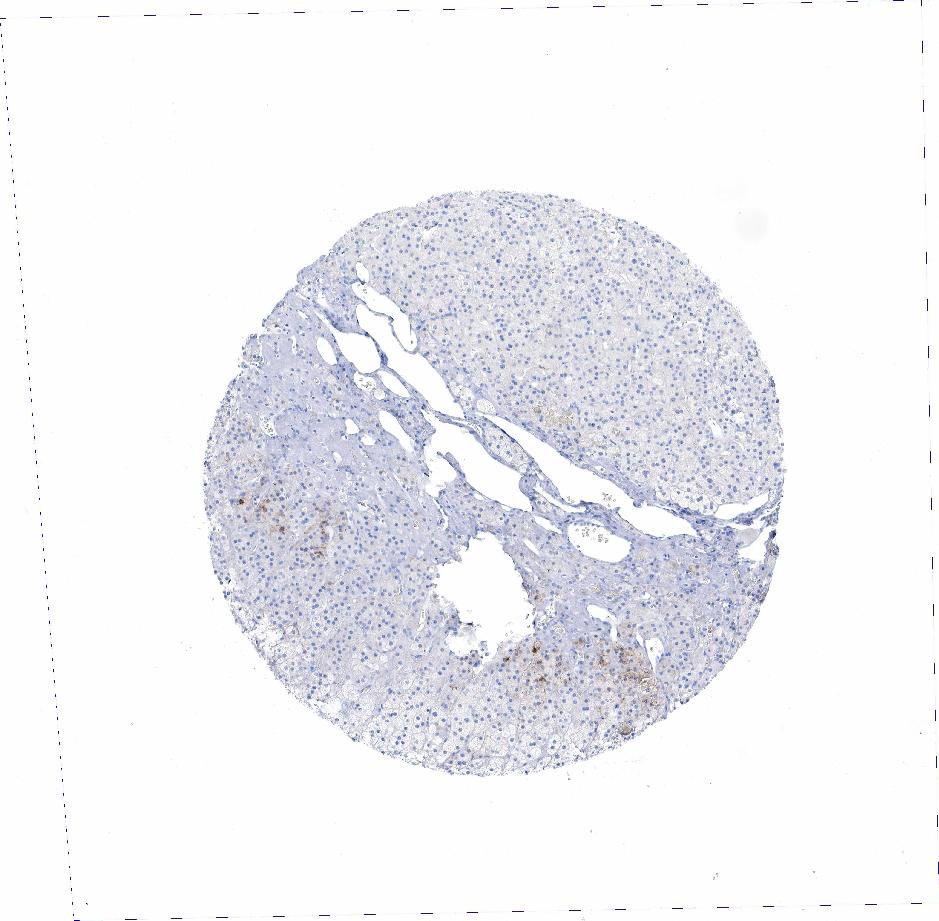

ADRENAL GLAND - Antibody stainingi

Antibody staining in the annotated cell types in the current human tissue is reported as not detected, low, medium, or high, based on conventional immunohistochemistry profiling in selected tissues. This score is based on the combination of the staining intensity and fraction of stained cells.

Each image is clickable and will lead to virtual microscopy that enables deeper exploration of all samples and also displays staining intensity scores, fraction scores and subcellular localization as well as patient and tissue information for each sample.

Antibody HPA001605Antibody CAB000008Antibody CAB000030

Glandular cells LowMediumMedium